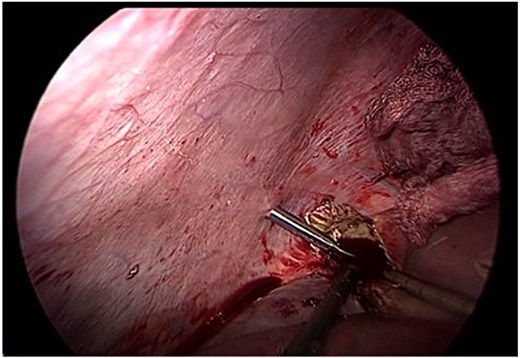

Following aspiration, the germinative membrane was carefully extracted using an endoscopic retrieval bag through a 10 mm trocar. The residual cavity was inspected with a 30° scope to detect any biliary communication (Fig. 3).

Endoscopic removal of the germinative membrane using an endobag through the 10 mm trocar. Inspection of the residual cavity was performed with a 30° laparoscope.